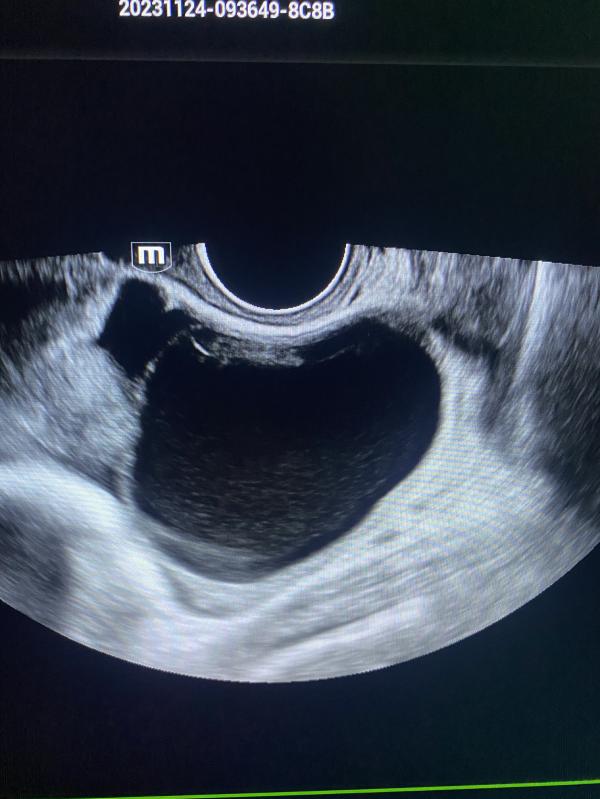

post image 1

На первом фото эндометриоидная киста до 6 см , в данном случае планируем беременность, так после операции есть риски снижения овариального резерва.